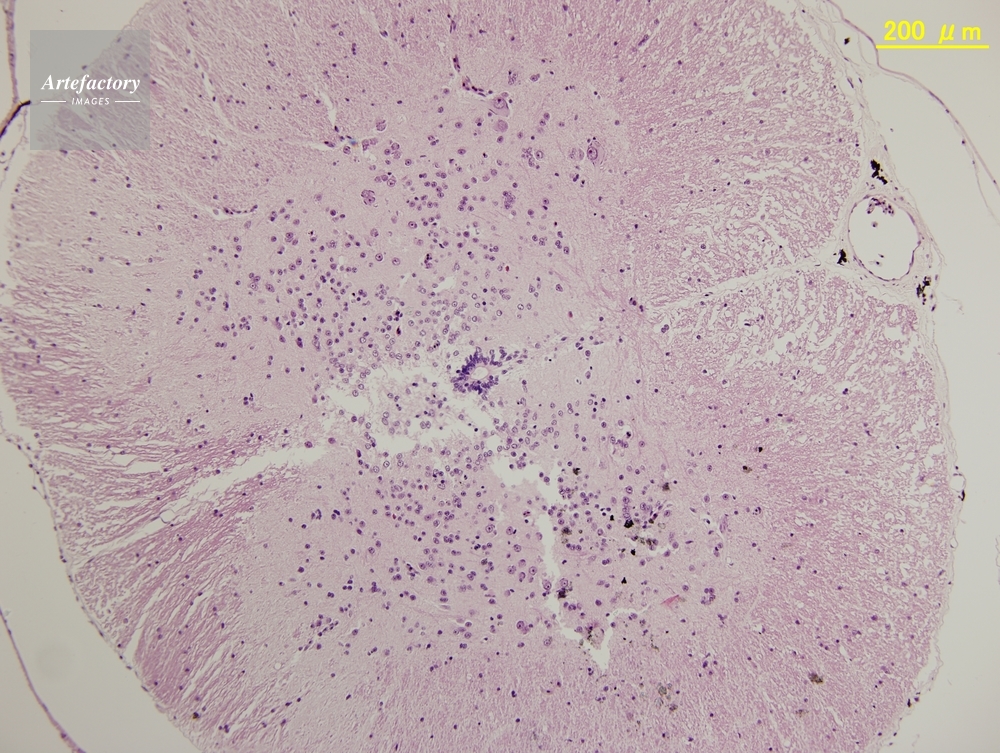

| 作品タイトル | ウシガエル,脊髄 | モデルリリース | なし | |